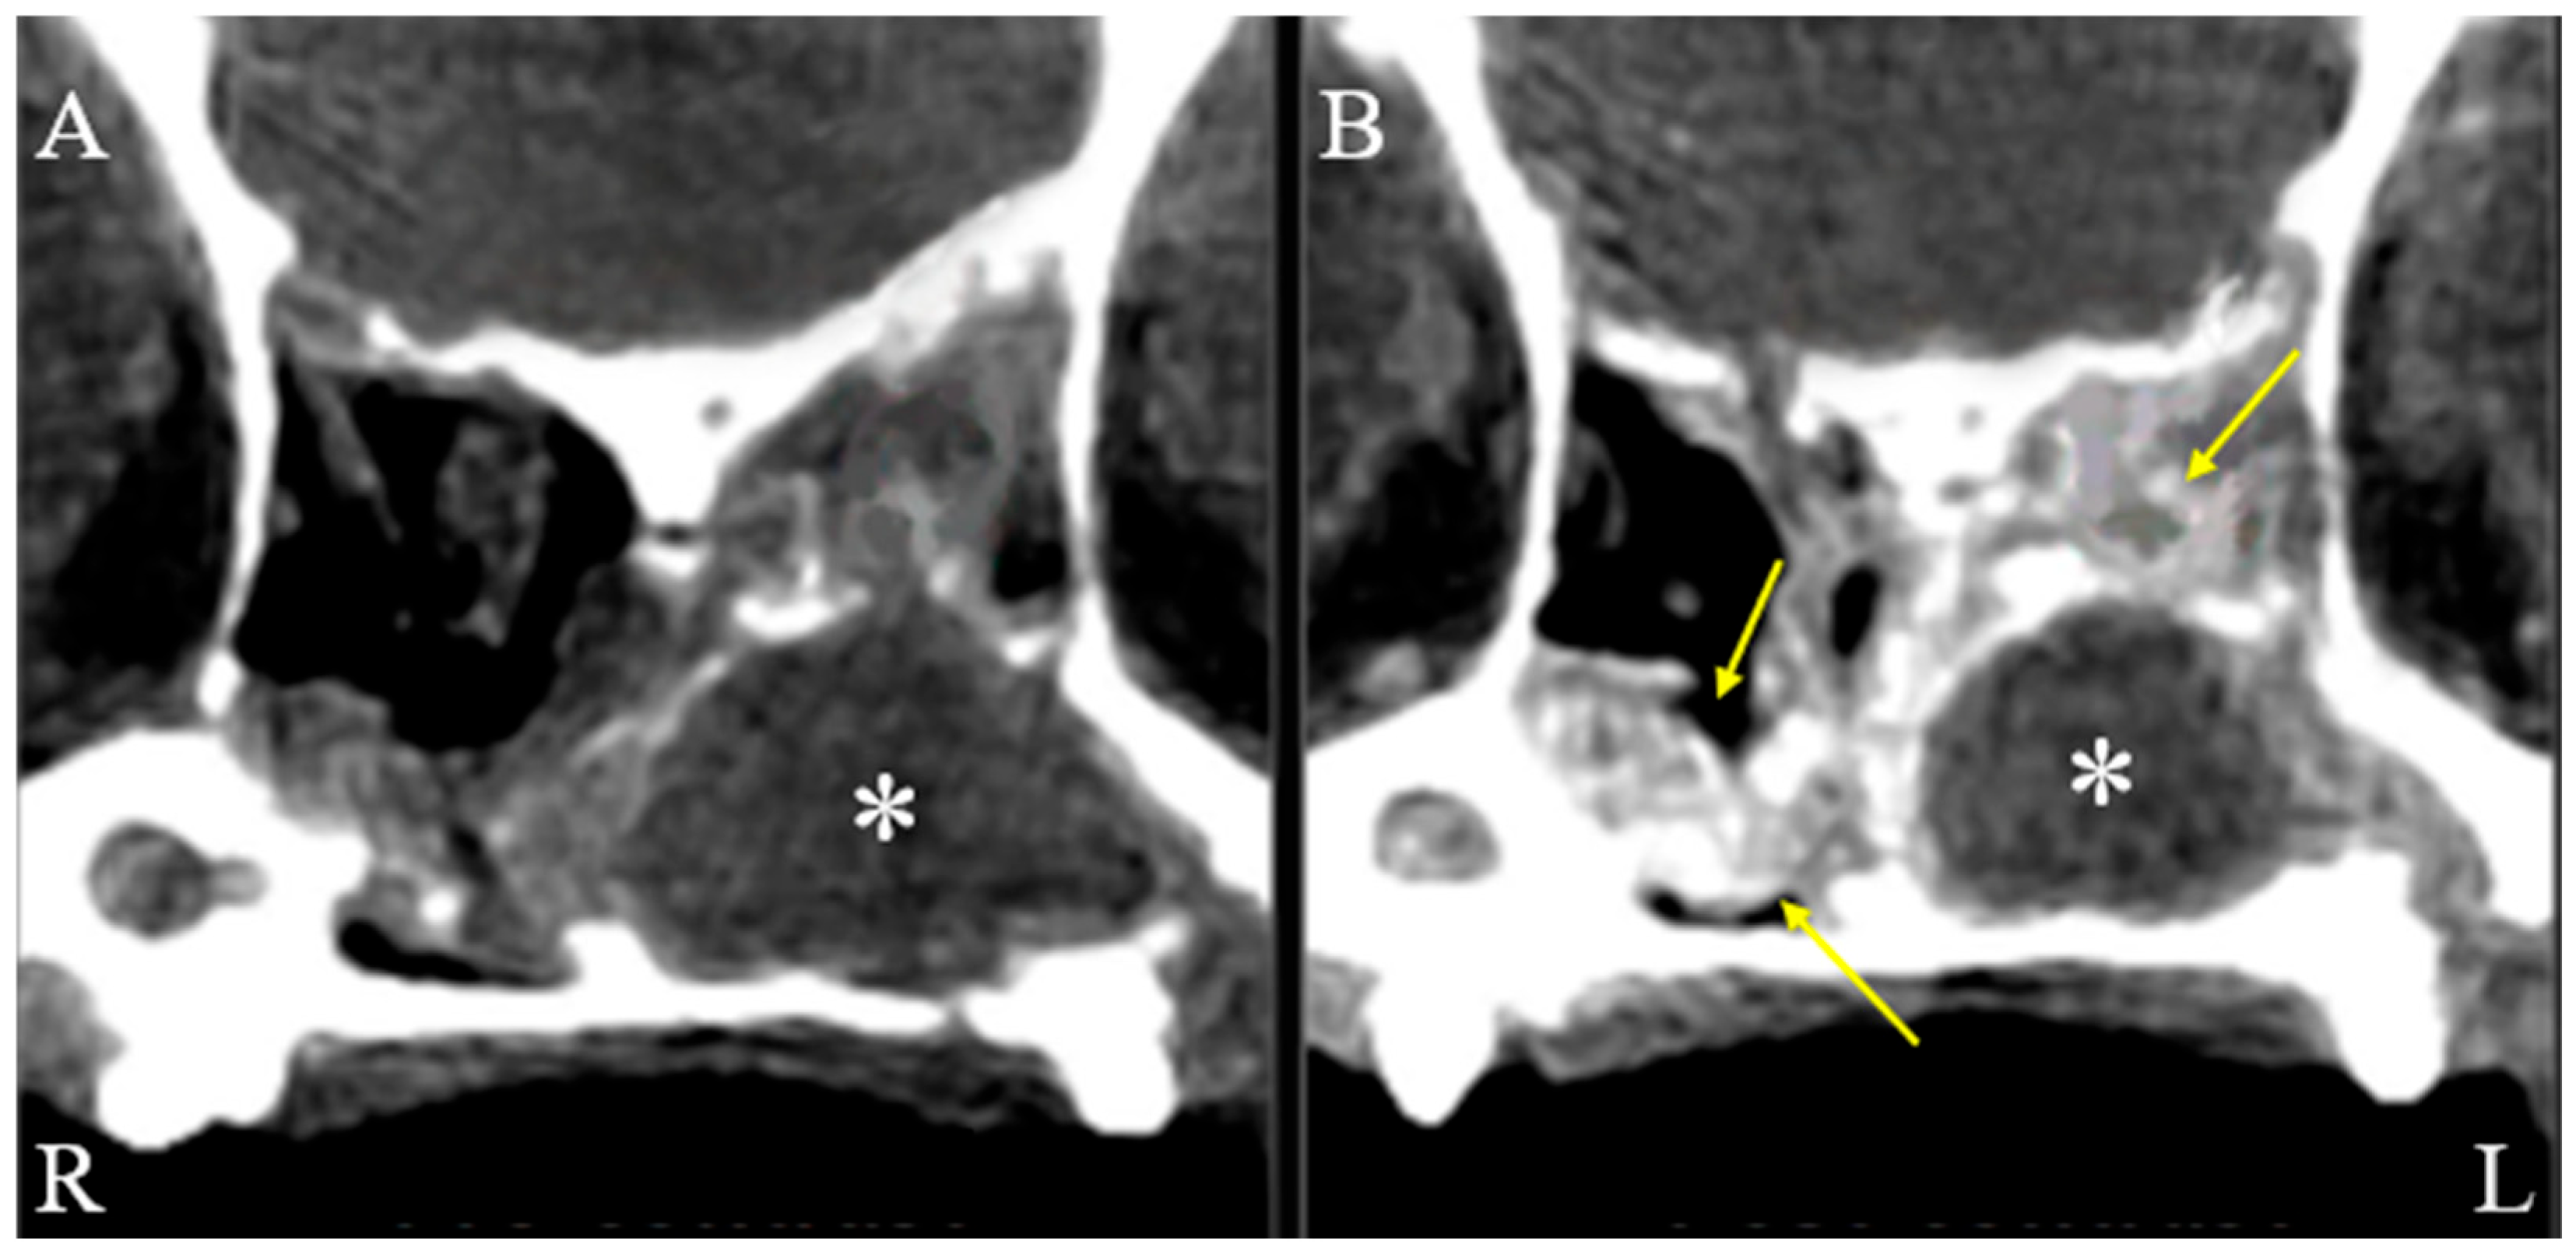

On physical examination, the dog showed serous nasal discharge in the left nasal cavity, nasal congestion, and intermittent reverse sneezing. Other physical examinations were unremarkable. Based on these findings, further computed tomographic (CT) evaluation of the nasal cavity was required. The dog was premedicated with butorphanol (0.2 mg/kg, intramuscular injection, Myungmoon, Seoul, Republic of Korea). Anesthesia was induced with propofol (6 mg/kg, intravenous injection, Myungmoon, Seoul, Republic of Korea). Intubation was performed, and anesthesia was maintained with isoflurane. CT (MyVet CT i3D, Woorien, Seoul, Republic of Korea) images of the nasal cavity were obtained. CT findings revealed a fluid-attenuated structure measuring 1.35 × 1.68 × 1.49 cm located in the mid-region of the left nasal cavity. The lesion involved the left nasal cavity, accompanied by soft tissue swelling in the adjacent left perinasal region, suggesting possible pathology in both the nasal cavity and surrounding soft tissues (Figure 1). The scan also revealed a fluid-attenuated mass occupying the nasal cavity, with evident contrast enhancement in the adjacent soft tissues, indicating pathological involvement of the surrounding structures (Figure 2).

Figure 1. Soft tissue window, post-contrast CT images of the dog’s head. Axial (A), sagittal (B), and dorsal (C) post-contrast CT images in the soft tissue window reveal a lesion in the left nasal cavity (R: right, L: left). A fluid-attenuated structure (asterisks) measuring 1.35 cm in height, 1.68 cm in width, and 1.49 cm in length is observed in the mid-region of the left nasal cavity. Additionally, soft tissue swelling is evident in the left perinasal region (yellow arrow), suggesting involvement of adjacent soft tissues.